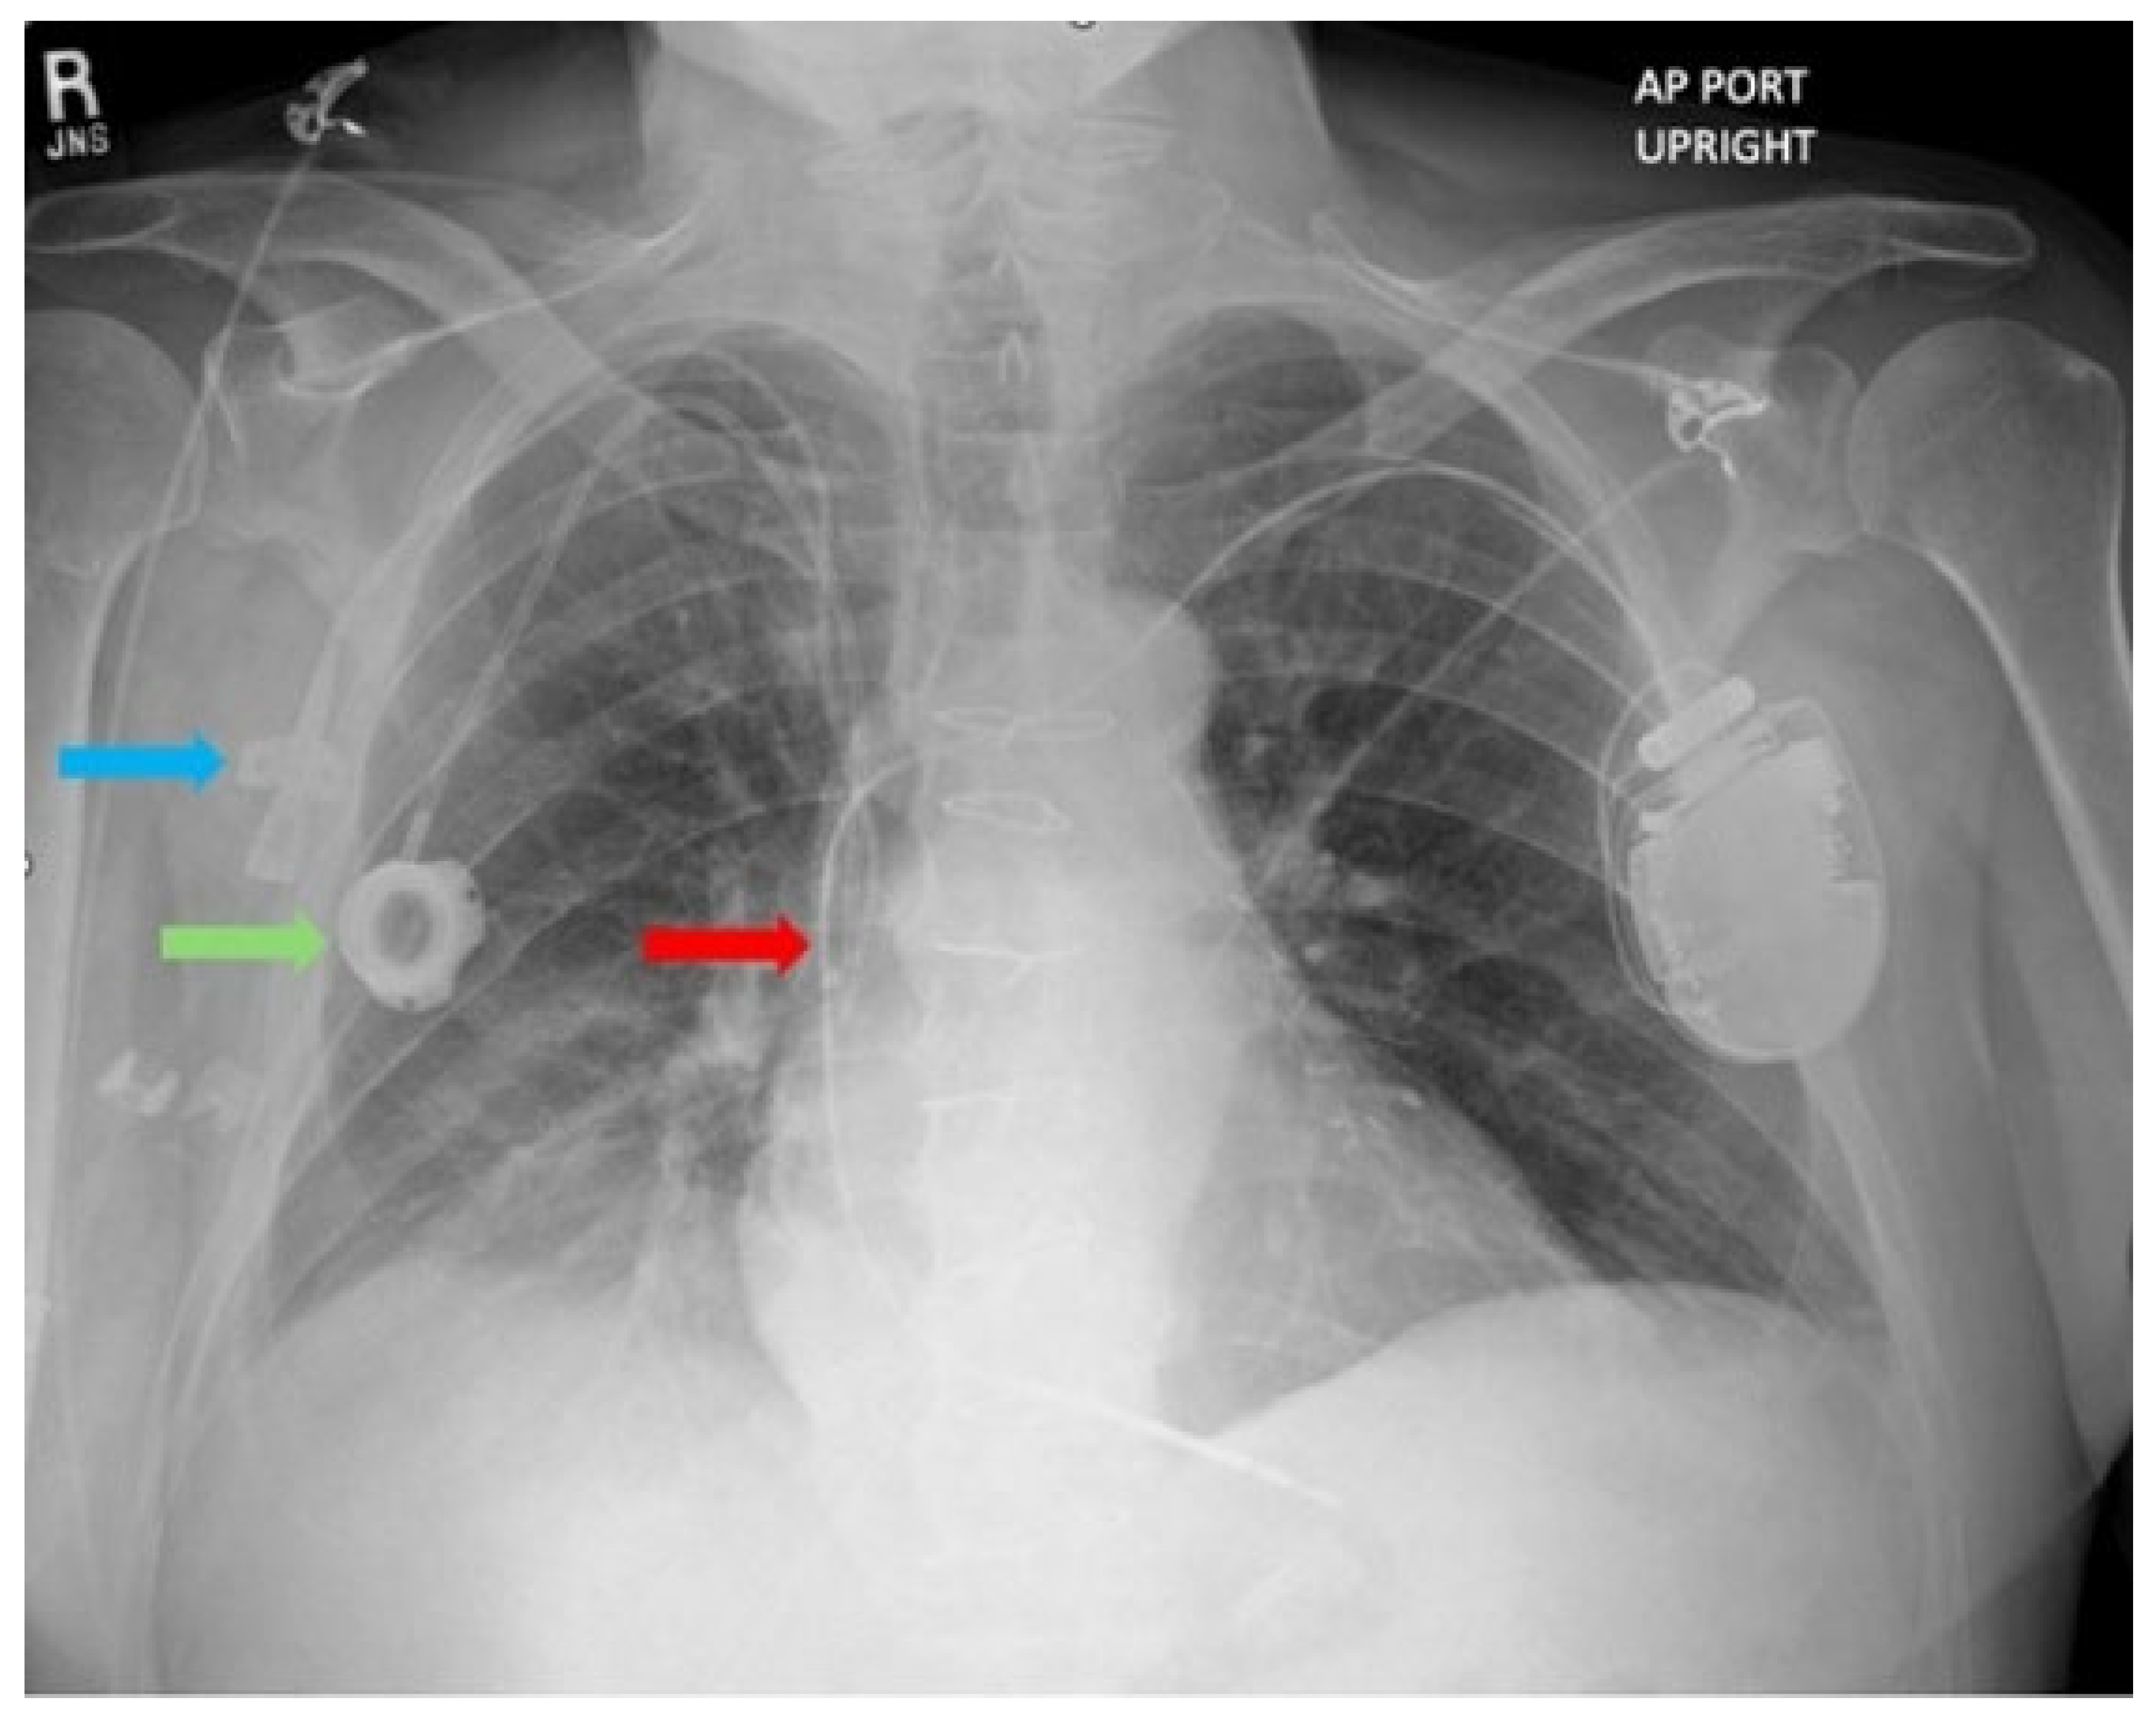

On Dobutamine, he showed stable hemodynamics with blood pressure 81/65 (70) mmHg, HR 79 bpm, respiratory rate 18/minute, temperature 36.4 °C, and SaO2 97%. His ECG showed sinus rhythm and poor R wave progression (Figure 1). Laboratory findings included a hemoglobin level of 11.8 g/dL, platelet count 160,000/µL, INR 1.4, creatinine 2.33 mg/dL, glomerular filtration rate (GFR) of 28 mL/min/1.73 m2, WBC 8900/µL, procalcitonin 0.12 ng/mL. Chest X-ray revealed a peripherally inserted central catheter (PICC) line, a prior central venous catheter (Port-A-Cath) inserted a month prior, and a single-chamber ICD lead positioned within the superior vena cava (SVC) (Figure 2). Routine echocardiography was performed to evaluate left and right ventricular function, valvular function, and to rule out cardiac masses and thrombus, determining the patient’s eligibility for LVAD implantation. He was deemed ineligible for a heart transplant considering his age, history of prior sternotomy, and Hodgkin’s Lymphoma in remission. Incidentally, echocardiography revealed a large, multilobulated, mobile thrombus measuring 35 × 30 mm in the right atrium (RA) of unclear origin. Further echocardiographic findings showed RA pressure 15 mmHg, RV systolic pressure 29 mmHg, and TAPSE 12 mm, suggesting only moderate RV dysfunction, an LVEF 17%, LVOT TVI 11.6 cm, Cardiac Output 4.1 L/min, Cardiac Index 2.09 L/min/m2, a mildly enlarged right ventricular chamber, moderately reduced left ventricular systolic function, and moderate tricuspid valve regurgitation. Elevation in RA pressure was felt to be increased in the setting of moderate TR and overestimates true filling pressures. No thrombus was detected in the other cardiac chambers. Upper and lower extremity Doppler ultrasound performed to investigate the source of the right atrial thrombus showed no evidence of deep vein thrombosis.

Figure 2. Chest X-Ray. Blue arrow: Peripherally inserted central catheter; Green arrow: Central venous catheter; Red arrow: Single chamber intracardiac defibrillator lead.